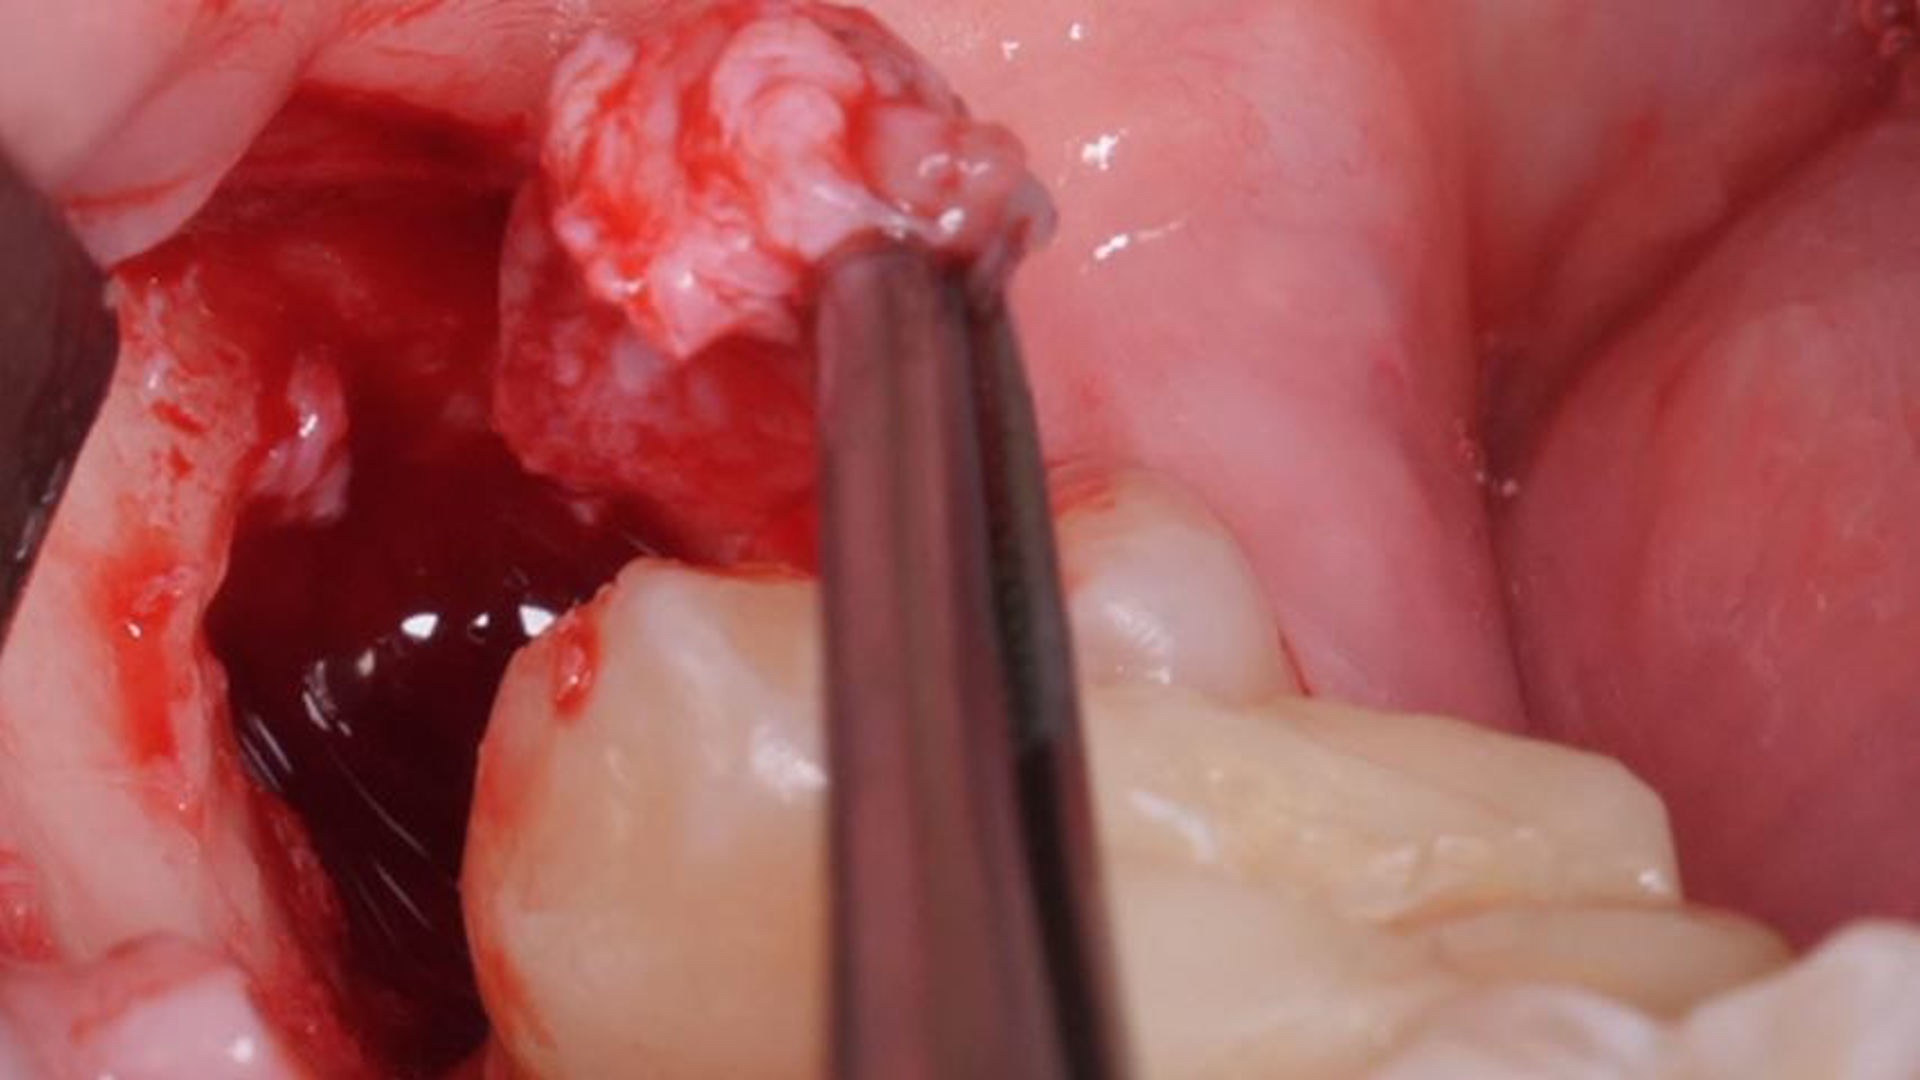

Lower right impacted third molar removal [4 8]

Surgical extraction of element 38: the importance of dental follicle removal